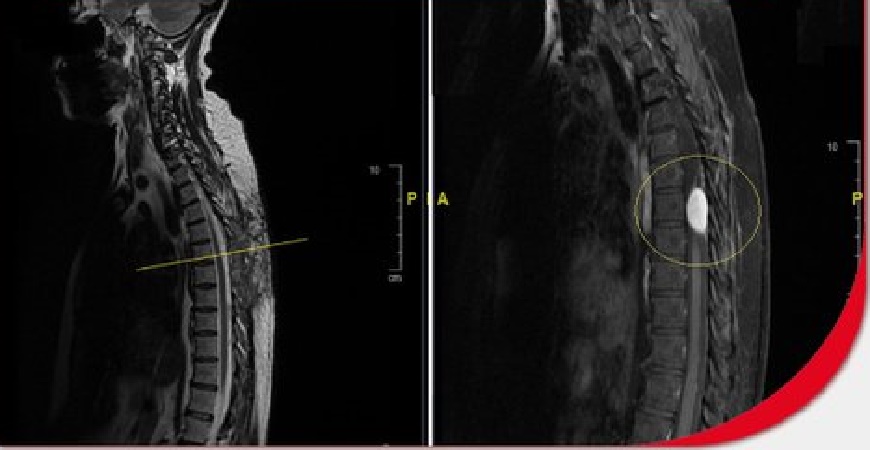

وأضاف أن نتائج الفحوصات أبانت وجود ورم من النوع الليفي بطول 4 سم متمركز في الفقرة السابعة من العمود الفقري ومتداخل مع الأعصاب، مسبباً ضغطاً شديداً على النخاع الشوكي، وهو الأمر الذي يؤدي بطبيعة الحال إلى الإصابة بالشلل التام -لا سمح الله – في حال إذا تأخرت المريضة في العلاج.